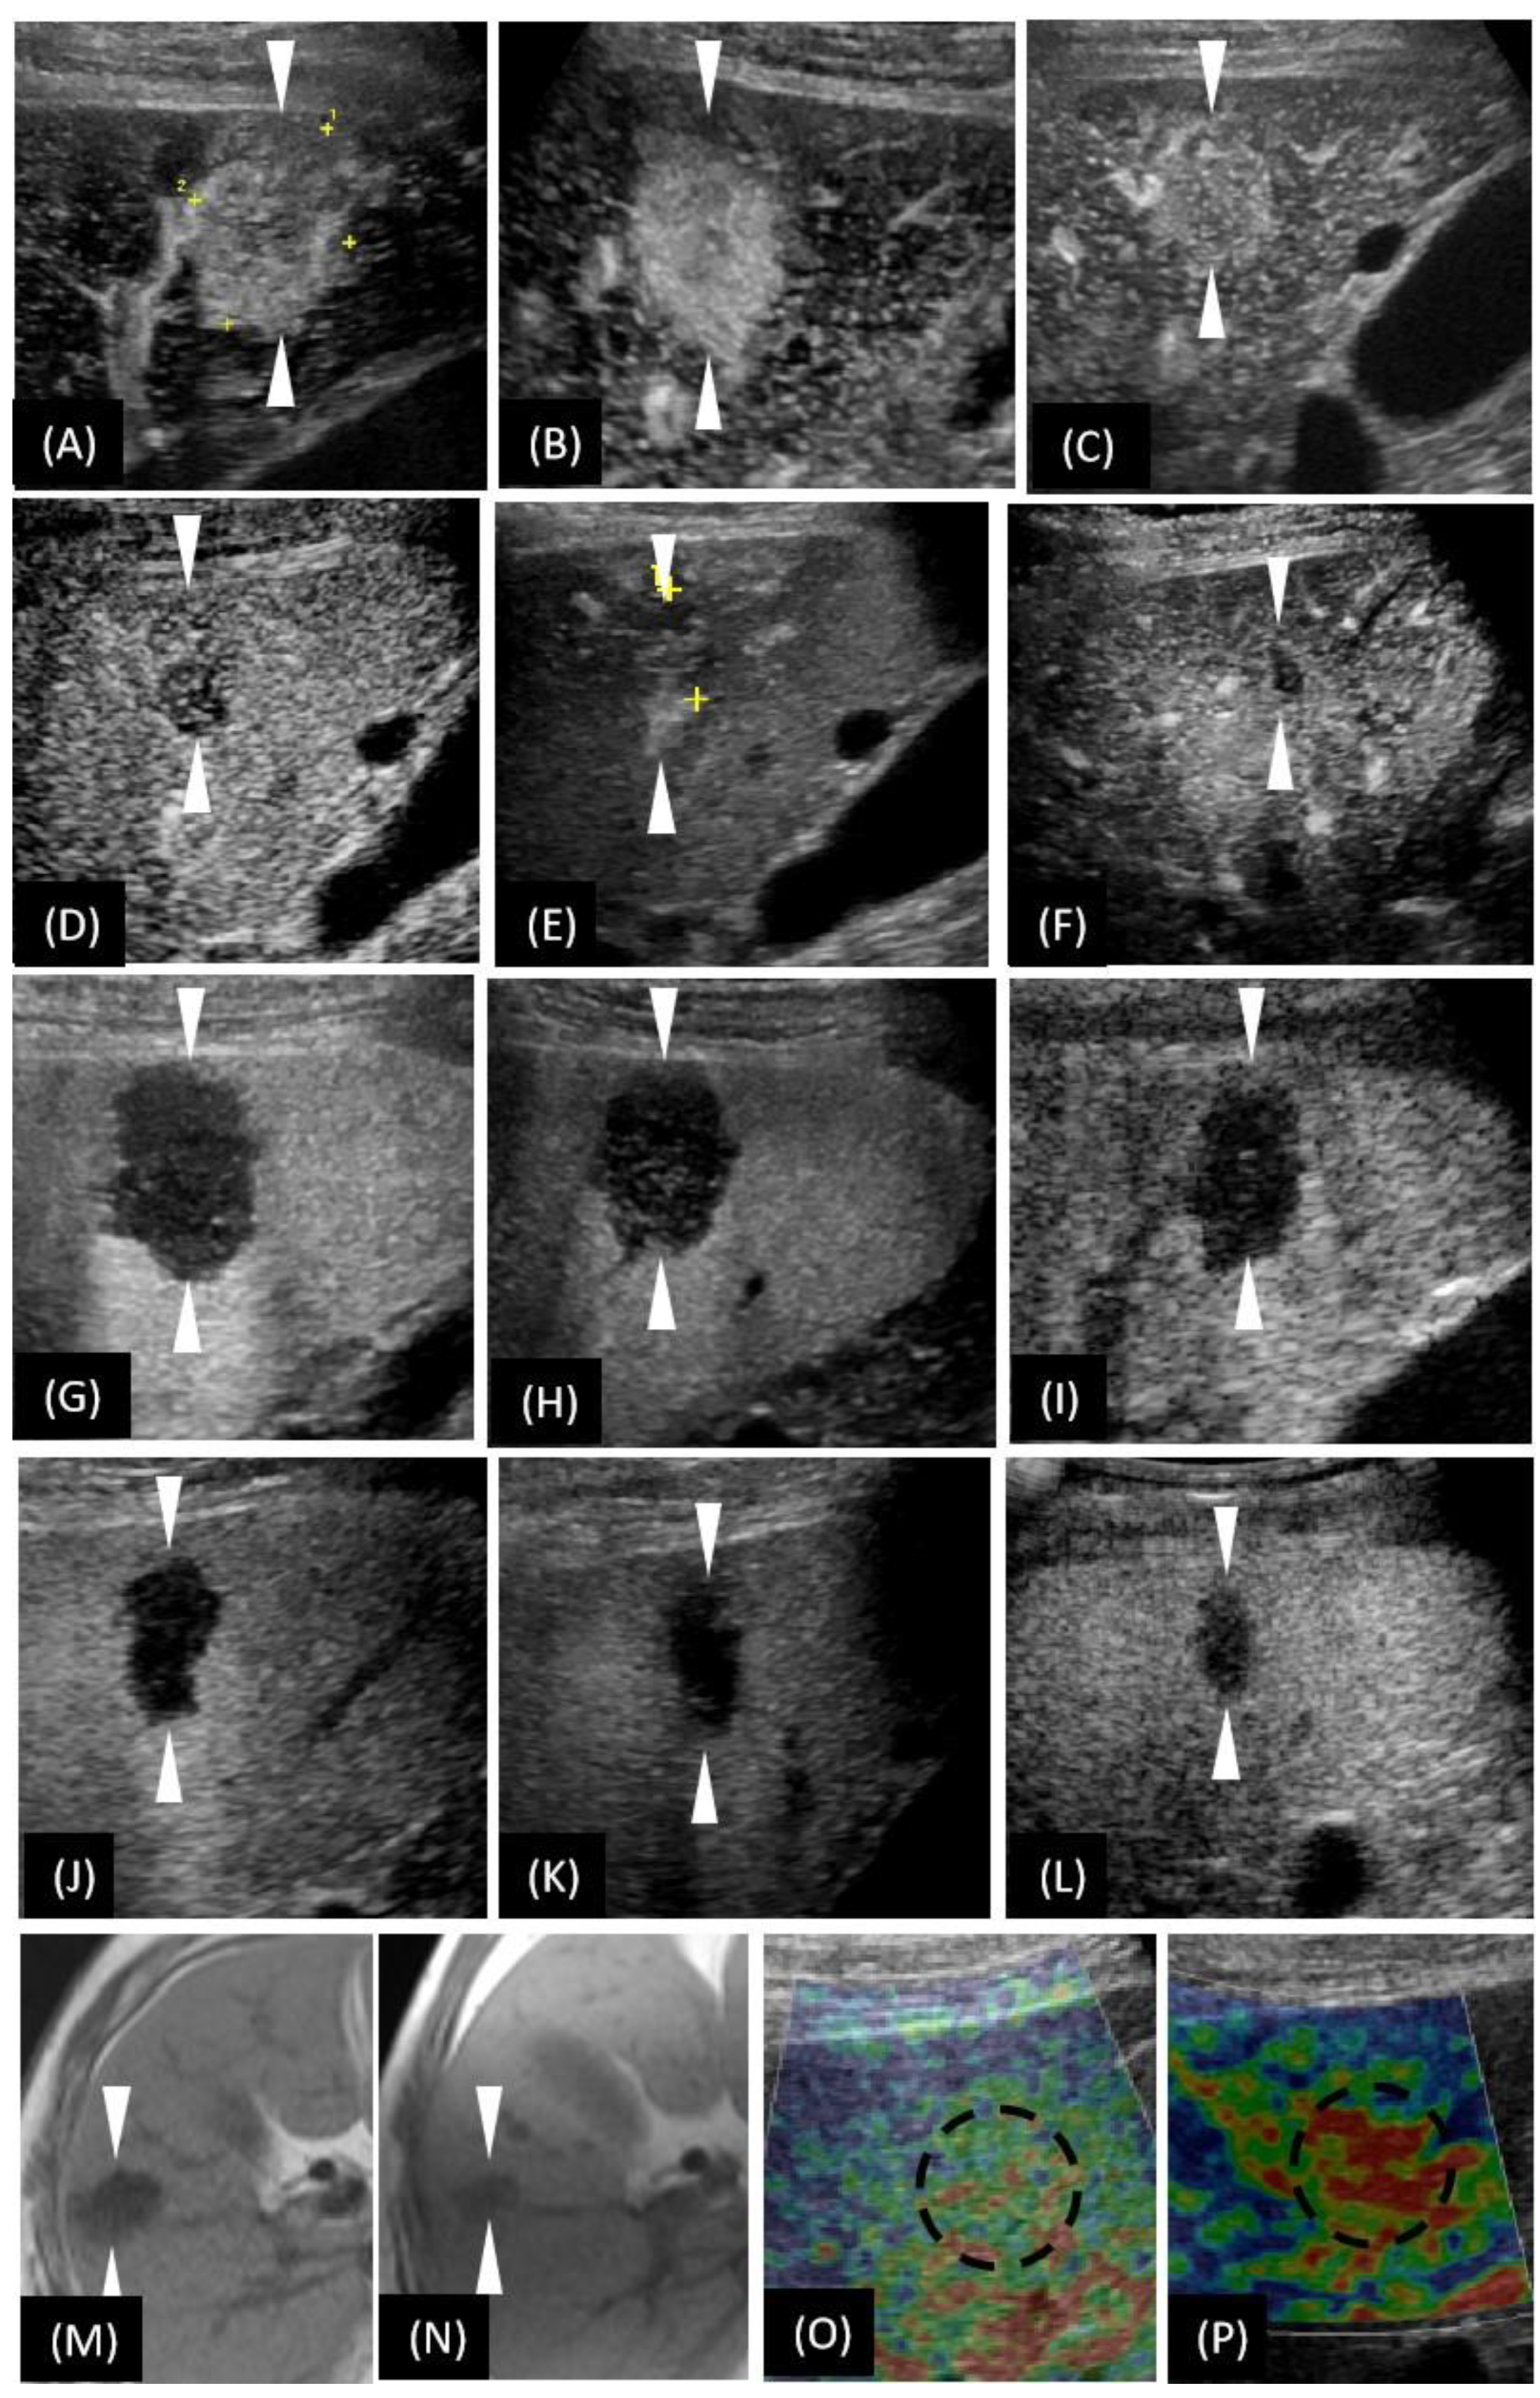

3.1. Our Case

3.2. The Characteristic Findings of CEUS in the Diagnosis of HSH

3.3. The Characteristic Findings of CT/MRI in the Diagnosis of HSH